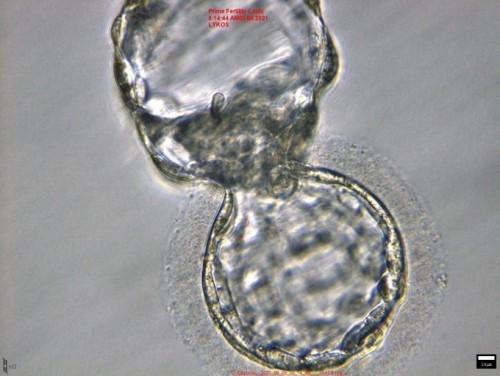

วิถีคุณแม่มีลูกยาก ใส่ตัวอ่อนระยะบลาสเกรด AA 🤸น้องเป็นเด็กชาย ตัวโต ตรวจโครโมโซมแล้วเรียบร้อย คุณหมอนัด ตรวจเลือดวันที่ 6/9/64 ค่าเลือดได้ 153 (หลังจากใส่ตัวอ่อนได้9วัน) ตรวจเลือดวันที่13/9/64 ค่าเลือดได้ 3,473 (หลังใส่ตัวอ่อนได้16วัน) คุณแม่ทำ#เด็กหลอดแก้ว ที่ #primefertilityclinic สำเร็จครั้งแรกหลังทำที่อื่นใส่มา3ครั้งแล้วแป่วว😂กับคุณหมอพูนเกียรติ คุณหมอเก่งมากๆคะ รีวิวสำเร็จทุกคนเลยระหว่างที่เรากำลังรักษาอยู่ ในใจคุณแม่ก็คิดนะว่า จะไม่สำเร็จที่เราไหมนะ แต่ว่า สำเร็จเช่นกันก็ปลื้มใจสุดๆ ที่คลินิกนี้ตัวอ่อนจะถูกเลี้ยงโดยนักวิทยาศาสตร์ชื่อดังในติ๊กต๊อก ซึ่งแนะนำคุณแม่ๆ ไปติดตามกันนะคะ ดูเพลิน อธิบายดีมาก ชื่อนี้ paweena.panrangsri ต่อมา คุณแม่ มีภาวะมดลูกวิรูป ก่อนใส่ตัวอ่อนคุณแม่ไปผ่าตัดมดลูกวิรูปผ่านกล้องมาคะ กับ #อาจารย์พัฒน์ศมา ผู้เชี่ยวชาญด้านมดลูกแห่งโรงพยาบาลวชิระ คุณหมอจะเชี่ยวชาญด้านมดลูกมากๆ เก่งมากท่านนี้ หลังผ่าตัดเว้น1เดือนก็ใส่ตัวอ่อนเลยคะ ผ่ามาวันที่21/6/64 และสุดท้ายนี้ คุณแม่เป็นสายมูไม่พลาด เช็คดวงชะตา ก่อนทำอะไรทุกสิ่ง ซึ่งปรกติแล้วก็ไม่เชื่ออะไรง่ายๆ แต่แม่นจริง ยอมรับ ไปหาดูในเพจ #เย้าแม่นยำ นะคะ *กว่าจะได้ท้องไม่ง่ายเลยจริงๆ 6ปี ที่คุณแม่รอคอย กับอิ๊กซี่ครั้งที่2 ใส่ตัวอ่อนครั้งที่4 ไปหาหมอตลอด เสียใจมาตลอด วันนี้ แม่ได้สมหวังสักที ❤️

ใส่ตัวอ่อนครั้งที่4 ทำอิ๊กซี่รอบที่2 (สำเร็จแล้วคะ) เด็กหลอดแก้ว